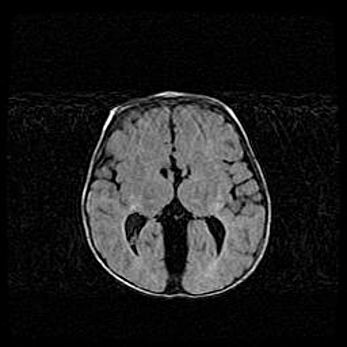

Множественные кисты обоих полушарий головного мозга, наибольшая из них в правой затылочной области. Ассиметричная атрофическая гидроцефалия.

Возраст: 7 месяцев

Вес: 5660 г

Пол: мужской

Окружность головы: 41,5 см

Срок гестации: 28-29 недель

Кисты головного мозга развиваются в результате многоочаговых некрозов вещества мозга и возникают вследствие перенесенной перинатальной инфекции, менингитов, энцефалитов, асфиксии, родовой травмы, расстройств мозгового кровообращения различного генеза. Образованию кист в веществе головного мозга плодов и новорожденных способствуют такие факторы, как высокое содержание в нем воды, недостаточная (или отсутствие) миелинизация и слабая астроглиальная реакция на повреждение.

Кисты могут сочетаться с гидроцефалией и другими поражениями головного мозга.